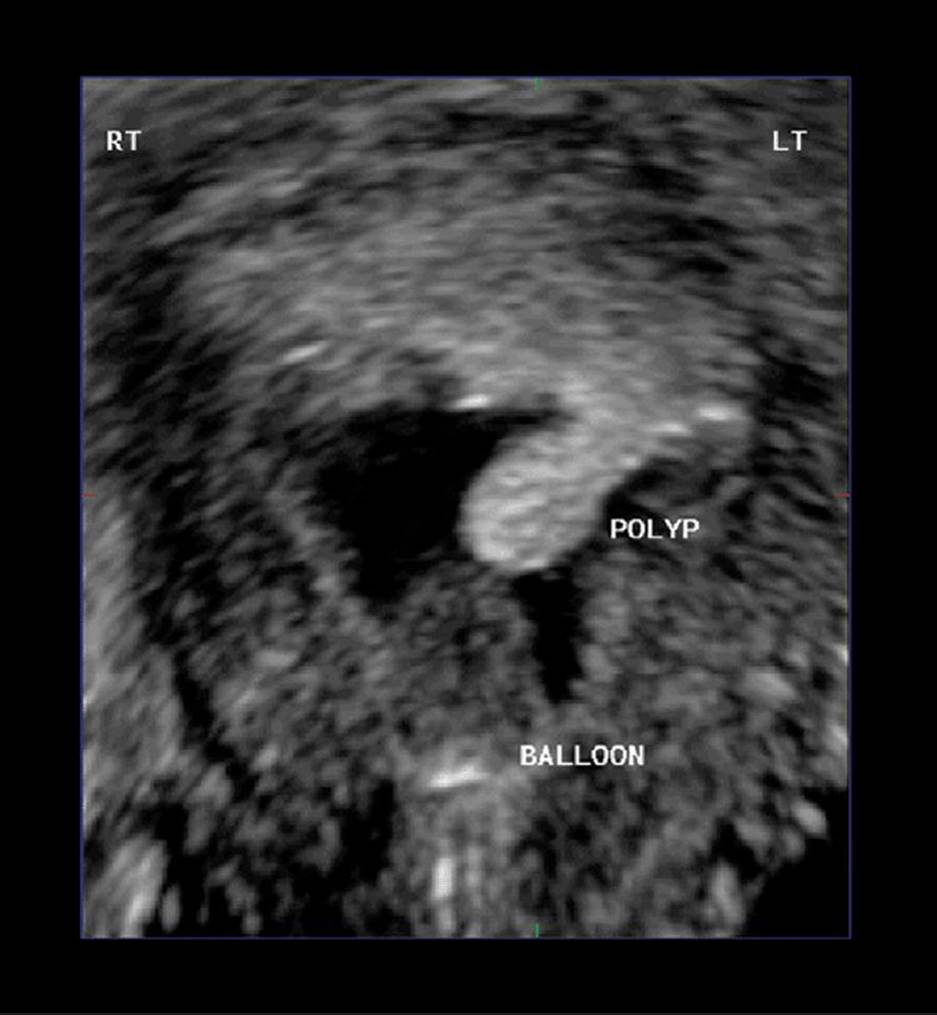

Three-dimensional sonography has many clinical applications in gynecologic disorders (Figs. 8–28 through 8–37). As in obstetrical 3D, gynecologic 3D affords depiction of the uterus and ovaries in any selectable scan plane, including those not readily obtained with 2D. These include improved depiction of endometrial masses such as polyps or submucosal fibroids, improved localization and calculation of changes in fibroid volume, enhanced depiction of tubal masses, intrauterine device localization, and uterine malformations. Three-dimensional depiction of tumor morphology and vascularity within ovarian masses has important implications in distinguishing benign from malignant masses.

FIGURE 8–32. Three-dimensional surface-rendered image obtained during sonohysterography showing polyp (arrow). (Courtesy of Philips Healthcare.)